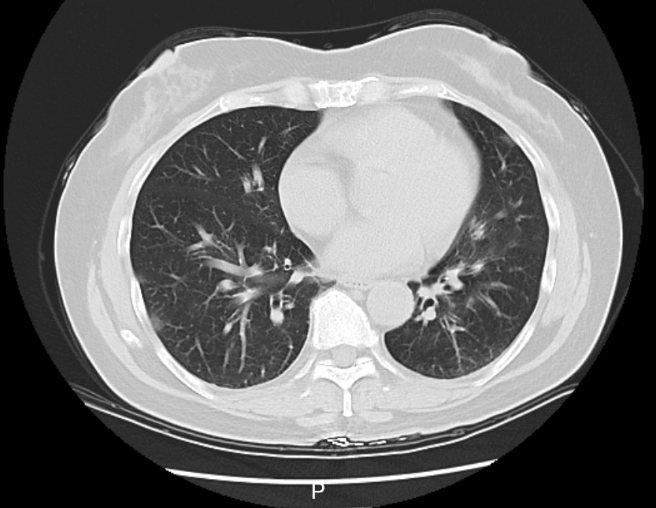

接诊的庞医生了解到,李阿姨在当地接受了一些治疗,但体温仍居高不下。家中同行的6个人,有5个人都先后发烧了。庞医生判断,李阿姨大概率是得了传染性较强的呼吸道疾病,立即给她安排了血常规、相关病毒抗原检测,以及更清晰的肺部CT检查,以便进一步了解病情。

李阿姨肺部CT影像

检测结果显示,李阿姨已经得了病毒性肺炎,甲型流感病毒核酸呈阳性。这一下,罪魁祸首找到了,是甲流搞砸了这一家人一次本该圆满的旅行。